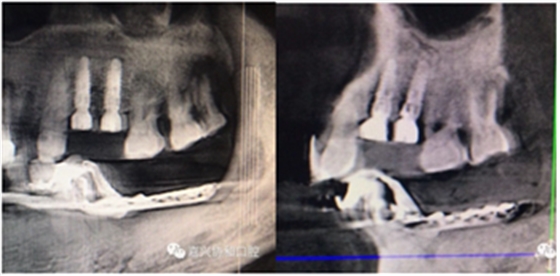

愈合基臺(tái)的置入及縫合

術(shù)后種植體位置與術(shù)前設(shè)計(jì)一致